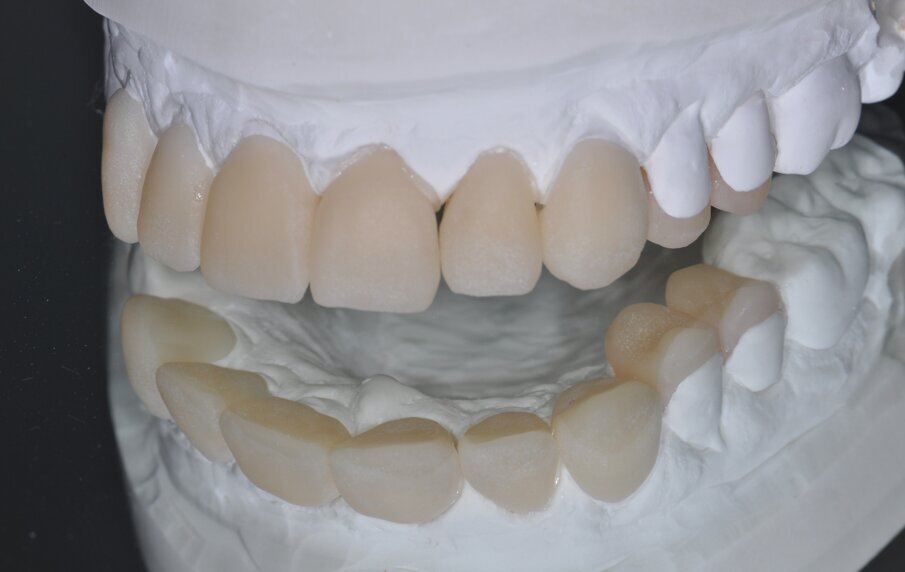

Fig. 10: Milled restorations fit on the model

The restorations were milled from blocks of a zirconia-reinforced lithium silicate (Celtra Duo; Dentsply Sirona Restorative) of A2 HT shade, finished with water-cooled diamond cutters and adapted on the model (Figs. 10 and 11).